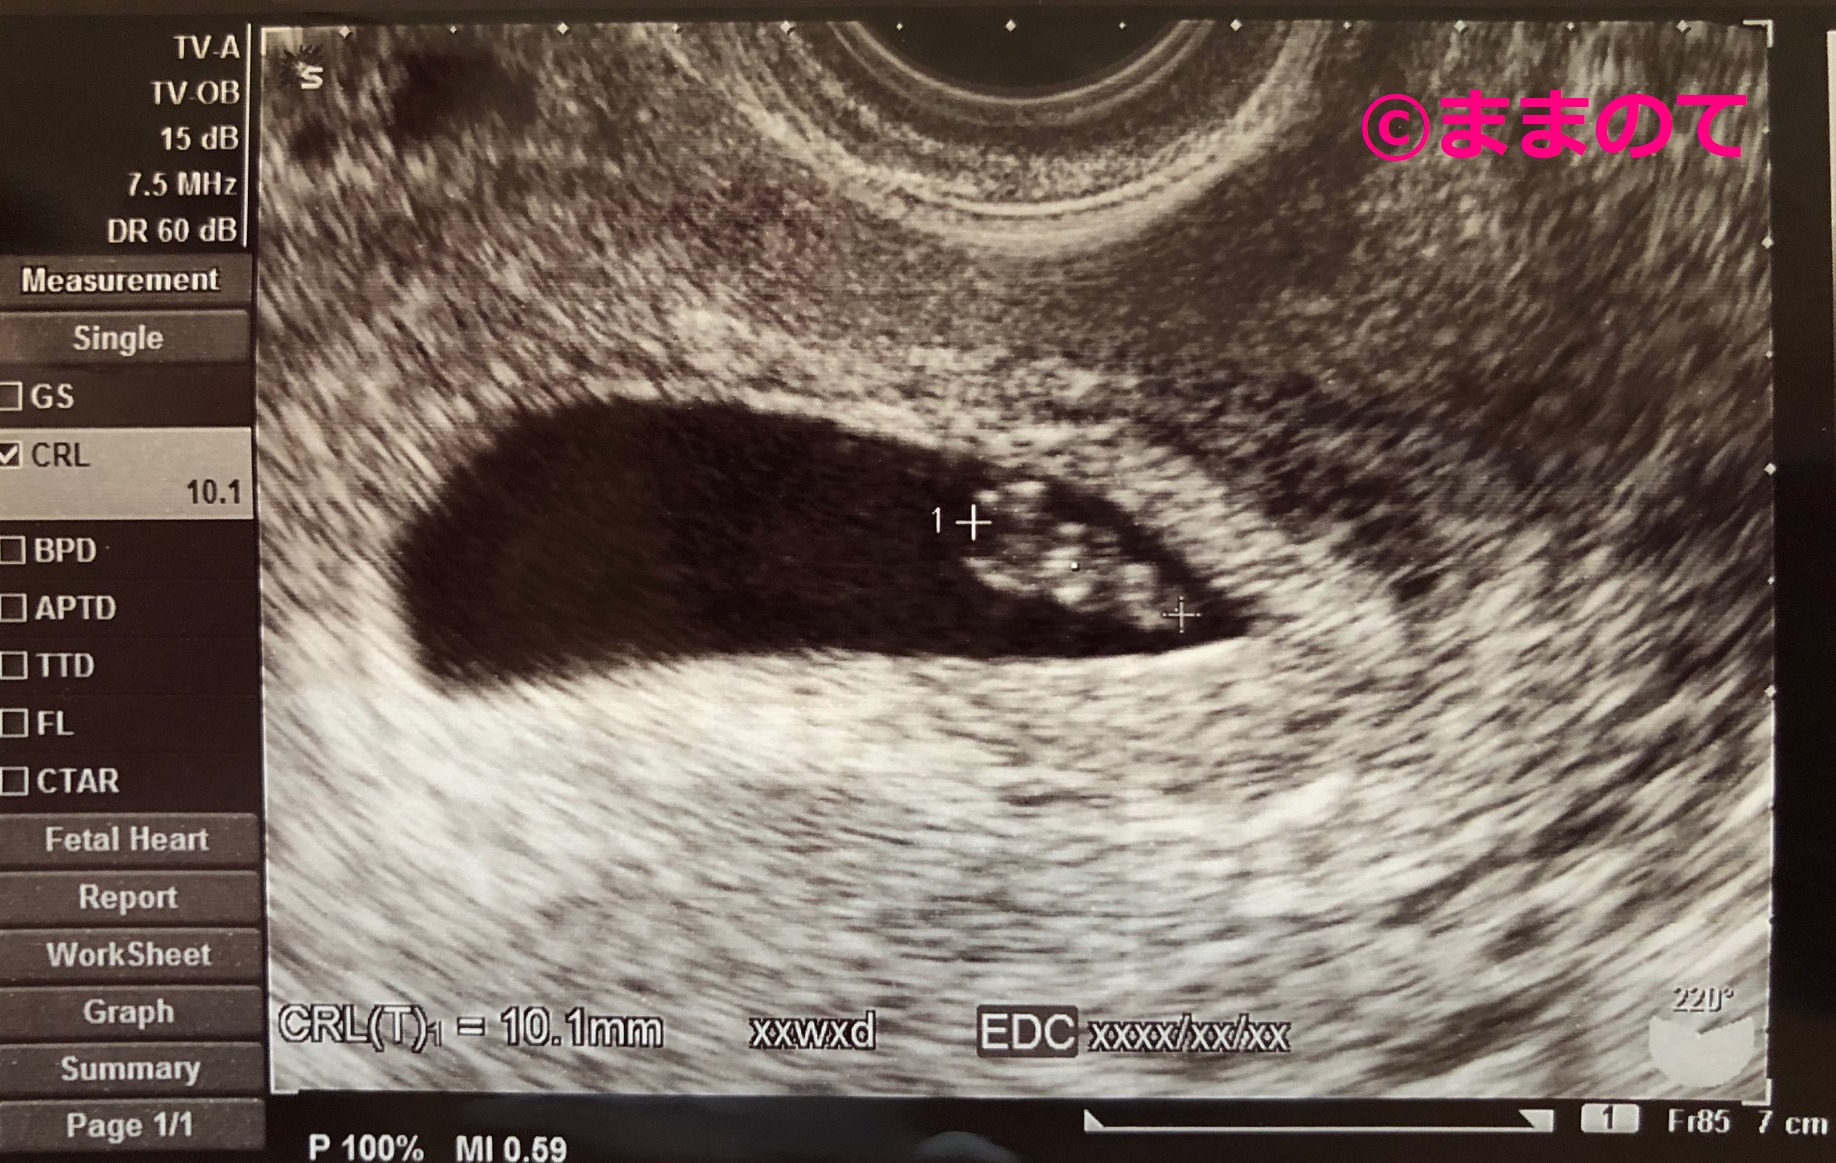

妊娠7週の赤ちゃんのエコー画像

実際の画像を例に、エコー写真の見方を解説します。

上の画像は妊娠7週3日のエコー写真です。ちょうどCRL(頭殿長)を測っている場面なので、左側の十字カーソルは頭のてっぺんに、右側の十字カーソルはおしりの部分に合わさっています。首になる部分が少しくびれていて、頭と身体がわかれ始めている様子がわかりますね。